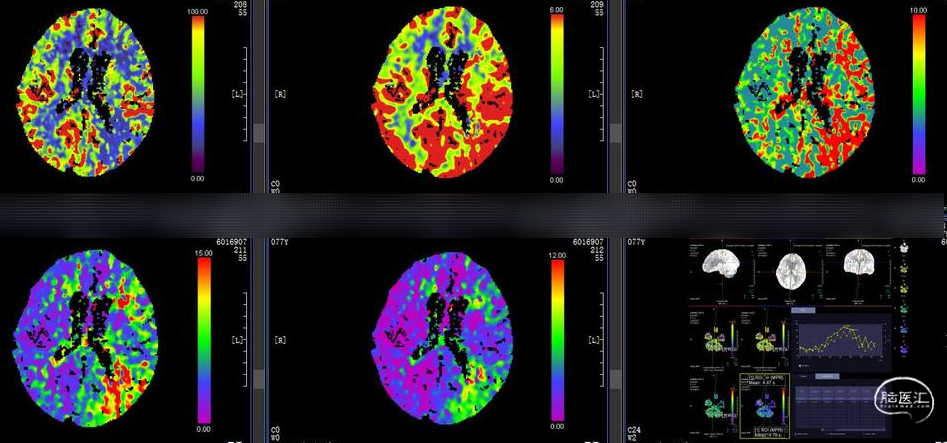

影像资料

术前MRI:双侧小脑半球、延髓急性梗死

术前复查头颅MRI+MRA:双侧小脑半球梗死较前进展,梗死范围增大。MRA提示基底动脉中下段重度狭窄。

术前高分辨MRI显示左侧大脑中动脉M1段重度狭窄,增强后斑块明显强化。